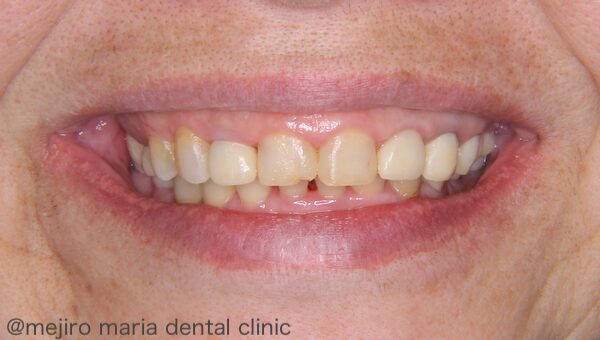

患者様は、自分の前歯が小さく、笑ったときに歯茎が大きく露出することが昔からコンプレックスだったそうで、専門的な治療を希望して、当院を受診されました。

スマイル時の写真では、歯肉が3〜5mmほど露出しており、いわゆる「ガミースマイル」と診断して治療介入することにしました。